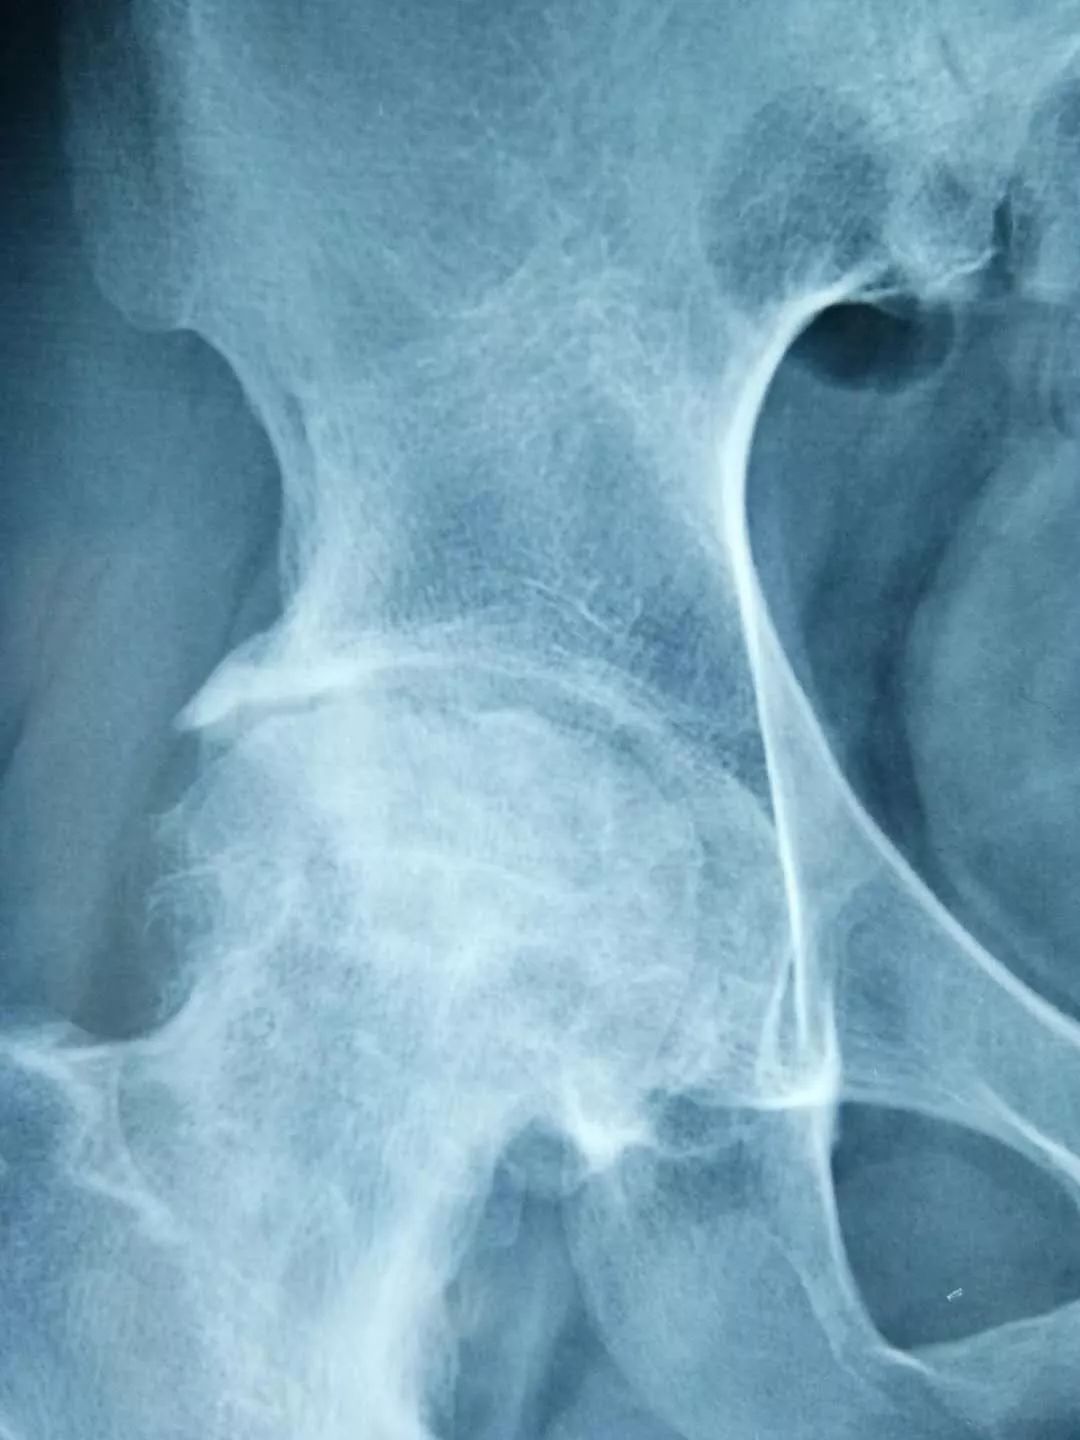

一名*安泰**的女性股骨头坏死患者,在儿女强力怂恿下来淄博找廉从希求医,一开始对“廉氏三联疗法”并不抱太大信心,但一个疗程结束后,患者便惊喜地发来医院检查的骨片,股骨头坏死部位纹理已明显开始致密均匀,病情有了很大好转。患者自此坚定了治疗信心,持续治疗3个月后痊愈。

经对118名患者跟踪调查,“廉氏三联疗法”对股骨头坏死的总有效率在92%以上;显效率(症状明显好转,功能障碍恢复)87%以上;病理改善率(影像显示骨密度增强)83%以上;临床治愈率(观察一年以上,症状消失,功能障碍恢复,可做日常家务及轻体力劳动)75%。

左图为治疗前,右图为治疗后。